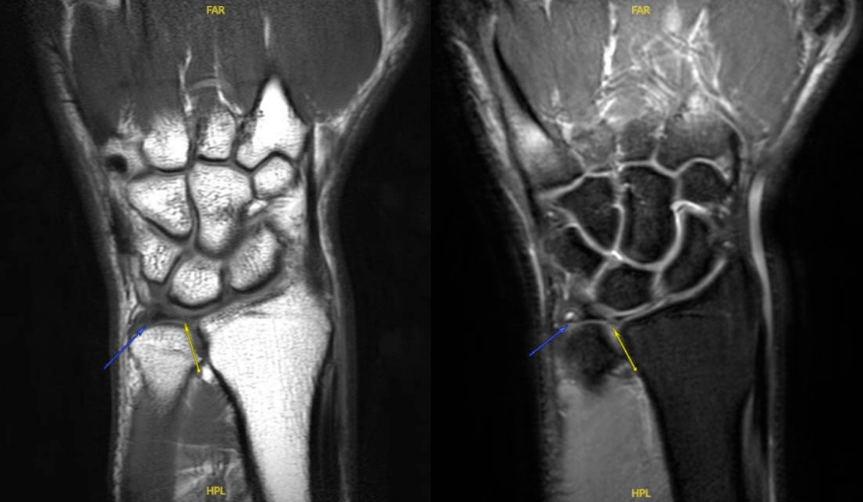

mr检查图中箭头所指为异常信号表现,提示tfcc损伤

图片尺寸863x502